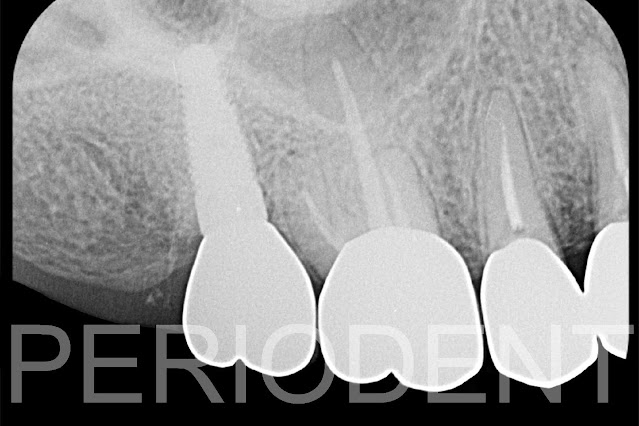

陳柏堅醫師發表右上第二大臼齒拔牙後鼻竇補骨的處理

1. 患者因為右上第二大臼齒假牙鬆動,有深度囊袋,發現牙根縱裂需要拔除

8. 八個月後植牙前準備